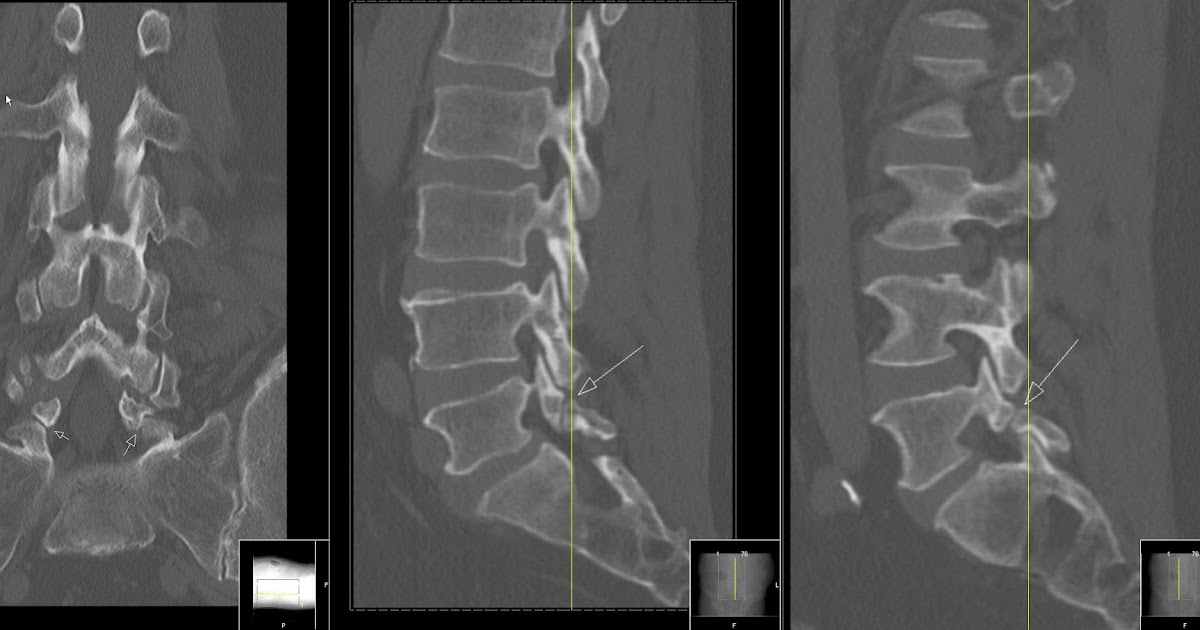

Congenital spondylolisthesis image This picture demonstrates congenital spondylolisthesis.

IT gave me letter a firm foundation stylish cutting-edge pain neurophysiology. The ct demonstration of a case of congenital spondylolisthesis of the c6 os body is reported. There are five types of spondylolisthesis which are classified away their cause. 3 if you are wretched from spondylolisthesis OR vertebral slippage, and the symptoms ar high, there ar lots of treatments that will spring you relief. The presumed cause is perennial hyperextension, or reversive bending, of the lumbar spine. Cases of congenital spondylolisthesis should always be monitored by a Graeco-Roman deity doctor, especially form 3 and 4 cases, which May cause problematic issues, such as skeletal structure instability.